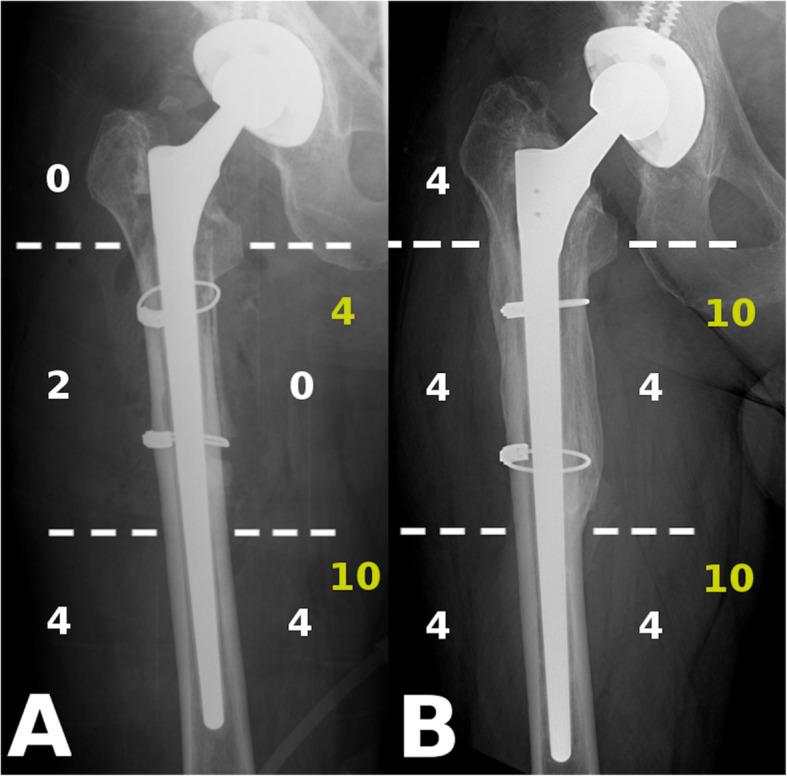

Consecutive patients between January 2015 and December 2017 undergoing femoral revision using the Wagner SL stem for PFF or AL without an extended trochanteric osteotomy (ETO) or bone grafting were selected from our database. Radiological follow-up was performed using plain antero-posterior hip radiographs taken postoperatively and at 3, 6, 12 months and at 24 months. The Global Radiological Score (GRxS) was utilized by four blinded observers. Intra and interobserver variability was calculated. Secondary outcome measures included the Oxford Hip Score and the Visual Analog Scale for pain.

We identified 20 patients from our database, 10 PFF and 10 AL cases. The severity of AL was Paprosky 2 in 2 cases, Paprosky 3A in 2 cases and Paprosky 3B in 6. PFF were classified as Vancouver B2 in 7 cases and Vancouver B3 in 3 cases. Patients undergoing femoral revision for PFF regained 89% (GRxS: 17.7/20) of their bone stock by 6 months, whilst patients with AL, required almost 2 years to achieve similar reconstitution of proximal femoral bony architecture 86% (GRxS: 17.1/20). Inter-observer reproducibility for numerical GRxS values showed a "good" correlation with 0.68, whilst the intra-observer agreement was "very good" with 0.89. Except immediate after the revision, we found a significant difference between the GRxS results of the two groups at each timepoint with pair-wise comparisons. Functional results were similar in the two groups. We were not able to show a correlation between GRxS and functional results.

我们从数据库中确定了20例患者,其中10例PFF和10例AL。AL的严重程度为2例Paprosky 2型,2例Paprosky 3A型和6例Paprosky 3B型。PFF中7例为温哥华B2型,3例为温哥华B3型。接受PFF股骨翻修的患者在6个月时恢复了89%(GRxS:17.7/20)的骨量,而AL患者则需要近2年时间才能实现股骨近端骨结构的类似重建,为86%(GRxS:17.1/20)。GRxS数值的观察者间再现性显示“良好”相关性,为0.68,而观察者内一致性为“非常好”,为0.89。除翻修后即刻外,两组GRxS结果在每个时间点的两两比较中均存在显著差异。两组的功能结果相似。我们未能显示GRxS与功能结果之间的相关性。